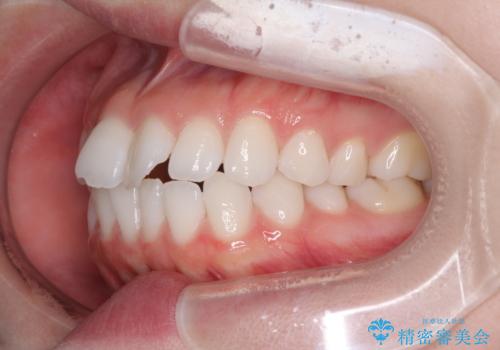

治療開始から4ヶ月ほどで概ね歯列が整い、その後の3ヶ月で細かい部分を仕上げていきました。

短期間で綺麗に仕上がり、患者様には大変満足していただきました。